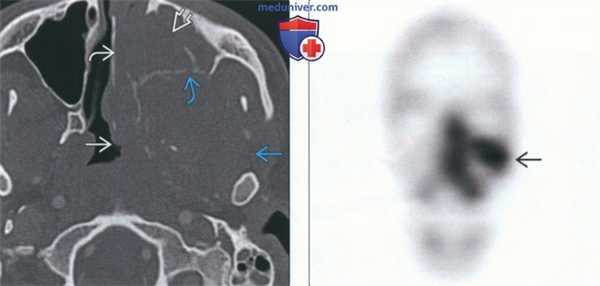

(Справа) Рентгенография в боковой проекции: у этого пациента с необычно медленно растущей саркомой Юинга рентгенографические изменения не визуализируются. Здесь отсутствуют, как признаки костно-деструктивных изменений, так и периостальной реакции. Жировые плоскости не смещены. Однако боль в руке сохранялась, что потребовало дополнительного обследования. (Слева) Сцинтиграфия в ПЗ проекции: у этого же пациента визуализируется зона патологического накопления в среднем отделе диафиза плечевой кости. Настораживает тот факт, что патологические изменения носят настолько расплывчатый характер, что не распознаются при рентгенографии, хотя могут указывать на высокую агрессивность процесса. Здесь следует подозревать саркому Юинга, поскольку патологический очаг имеет срединно-диафизарное расположение в плечевой кости подростка.

• Сцинтиграфия: активное накопление в первичной опухоли и любых костных метастазах

• ПЭТ/КТ: особенно эффективна при СЮ:

о СЮ: наибольшее из первичных костных опухолей стандартизованное значение накопления (в среднем 5,3)

о Используется для определения стадии СЮ:

- Более чувствительный метод для определения метастазов костей, по сравнению со сцинтиграфией (чувствительность при ПЭТ/КТ - 88%, при сцинтиграфии - 37%)